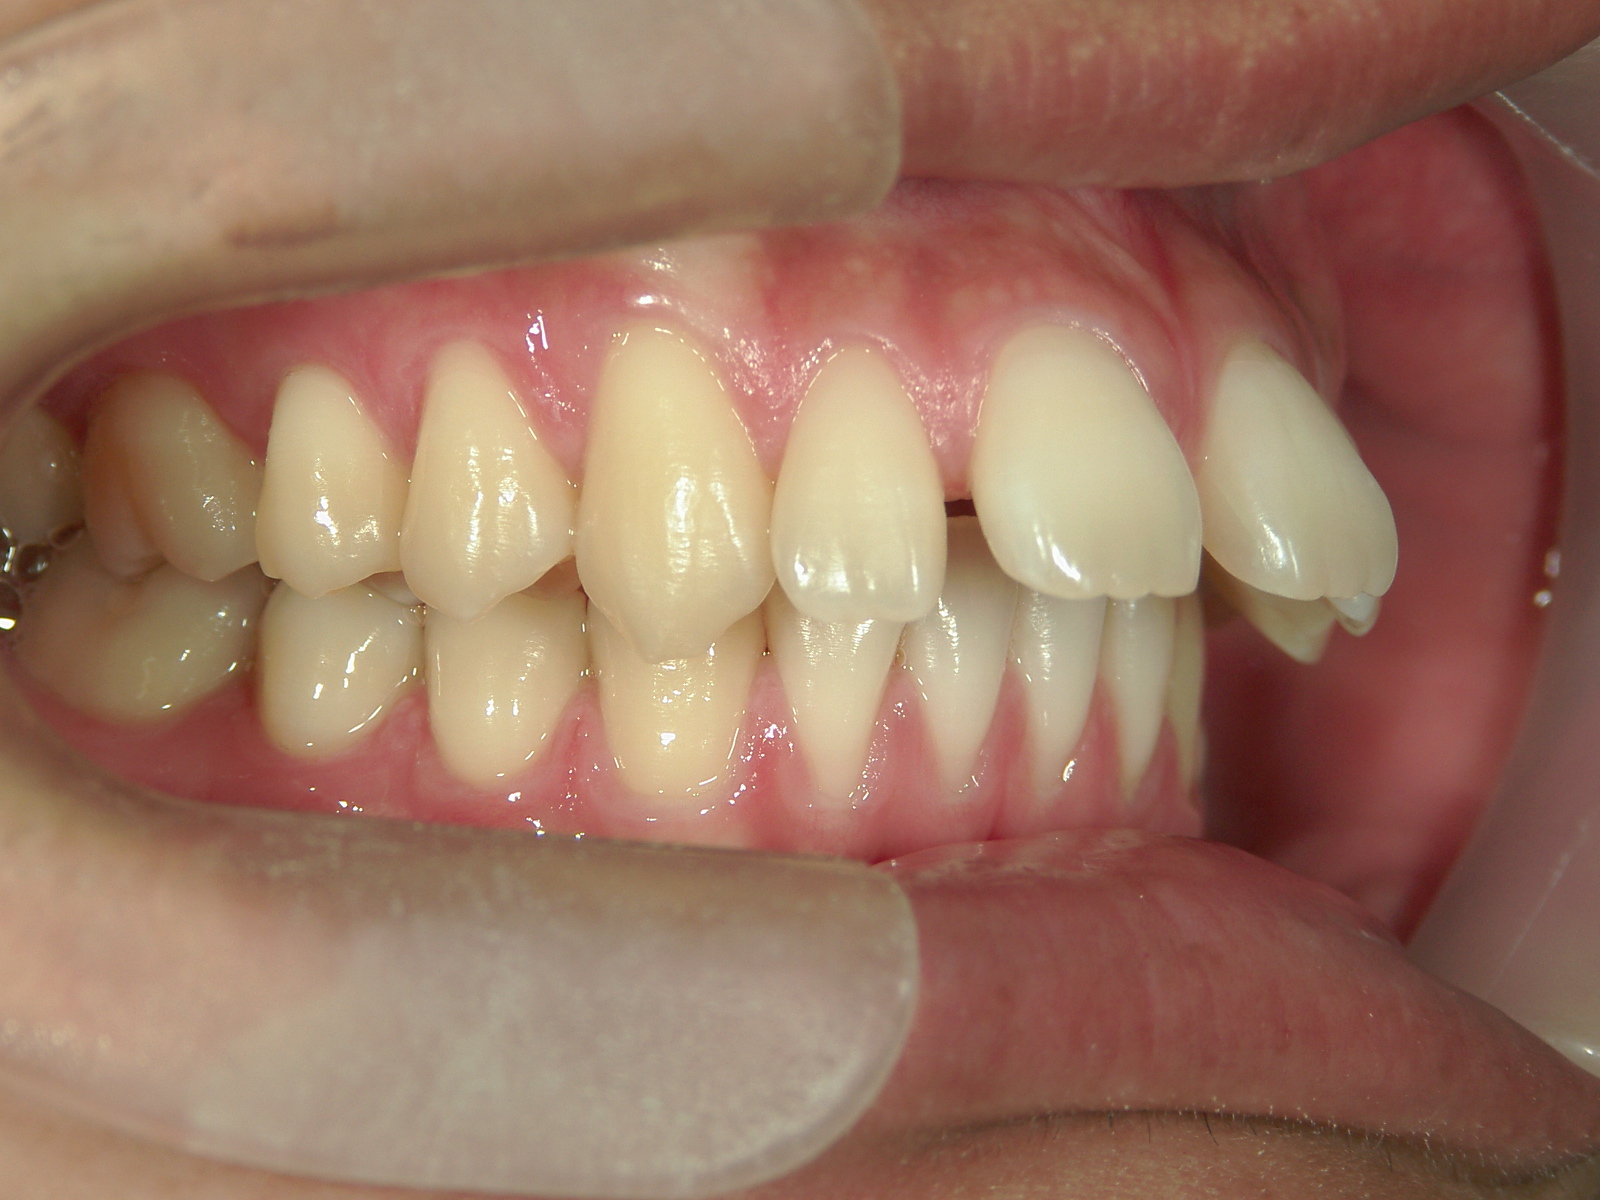

インビザライン矯正 症例(24)

主訴: 前歯の隙間が気になる。

左右上 第一小臼歯(2本)を抜歯。

カテゴリー : 隙間がある(空隙歯列)